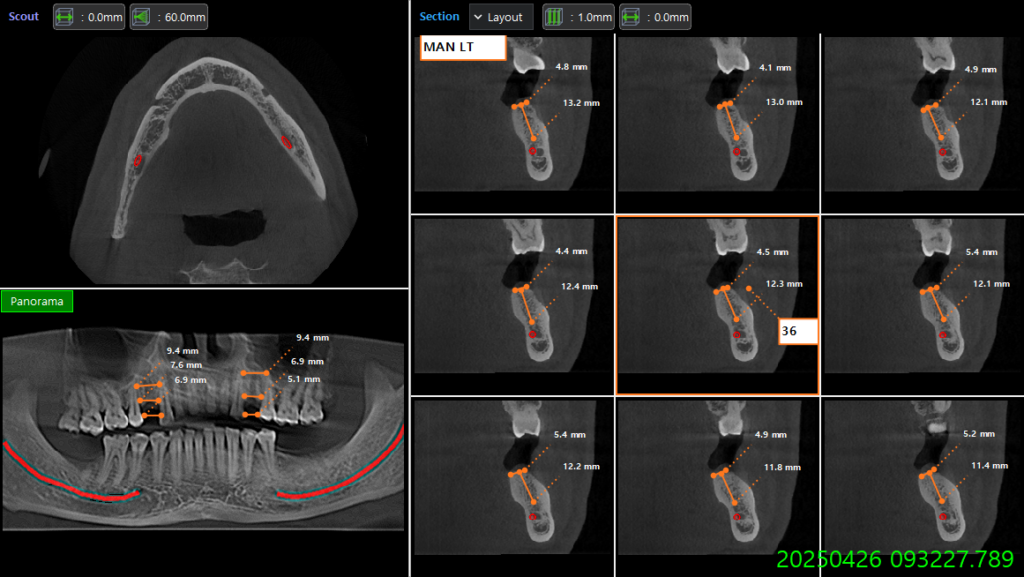

3D Surgical Guided Dental Implant - Why ?

3D guided dental implant is a modern addition in dental implant surgery. With Combination of jaw CT Scan and Oral 3D Scan a surgical guide prepared considering width and depth of the bone with precision placement of implant inside the jaw bone. It has multiple benefits:

- Reduce surgical time

- No soft tissue reflection and post operative bleeding

- Less chance of infection

- Reduce pain experience

- Avoid vital tissue injury